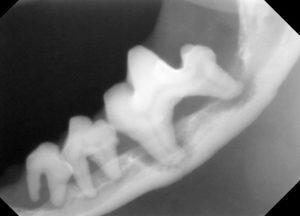

3.レントゲンでは、顎の骨が歯周病により骨折しやすい状態が確認されます。

4.下顎の顎先の骨も薄い状態です。

5.下顎の骨が溶けて、骨折しやすくなっています。

このように歯周病が進行すると、歯だけの問題でなく顎の骨が溶けてしまうため、顔の骨の骨折リスクが高くなり、治療にも慎重な歯科処置が必要になります。